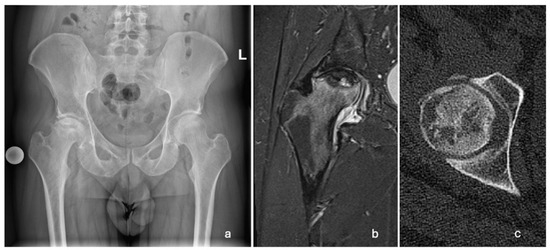

A 29-year-old Caucasian male patient presented to the emergency room in March 2022 with progressively increasing pain in his right hip over two months. Upon physical examination, the patient was limping and had extensively painful and limited rotations of the right hip joint. He was referred for an X-ray, a computed tomography (CT) scan, and magnetic resonance imaging (MRI) of the pelvis and both hips. The changes were indicative of stage 3 (Ficat and Arlet classification) ONFH of the right hip (Figure 1). The left femoral head was unaffected.

Figure 1. Radiographic images showing unilateral ONFH of the right femoral head. (a) AP pelvis X-ray taken in March 2022, showing a Ficat and Arlet stage 3 right ONFH; (b) T2-weighted MRI of the right hip taken in April 2022, showing ONFH with a subchondral fracture and femoral head collapse >2 mm (Association Research Circulation Osseous stage 3B); (c) CT scan of the right hip showing cystic deformation, the loss of continuity, and the applanation of the anterolateral femoral head.